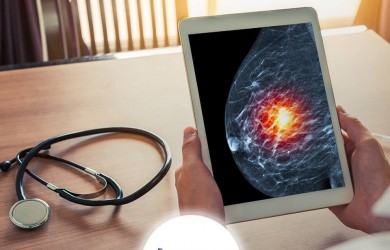

A biópsia mamária dói?

A Imax desde a sua fundação em 1991 tem o objetivo de valorizar a qualidade e o bom atendimento, com suporte tecnológico de equipamentos de última geração. Realizamos os exames de ultrassonografia em geral com doppler colorido, Radiologia Digital, Radiologia Pediátrica, Densitometria Óssea, Mamografia Digital e Biópsias de Mama, entre elas a Mamotomia.